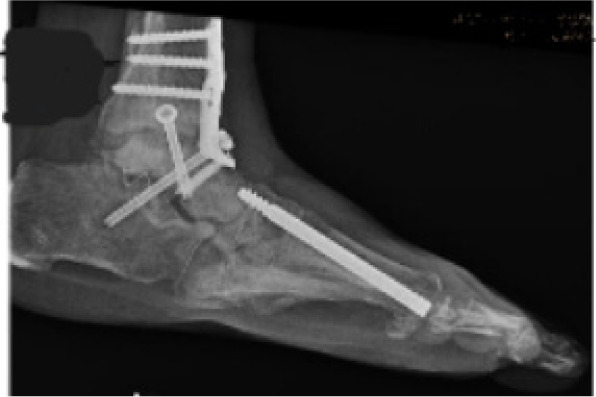

A three-stage surgical approach was performed to address both infection and mechanical instability. Stage one involved midfoot debridement with application of antibiotic-impregnated bone void filler for local antibiotic delivery and dead space management (Figure 5). In stage two, a multiplanar external fixator was applied to achieve gradual realignment of the midfoot and provide stable offloading of the ulcerated plantar surface (Figure 6). Finally, stage three included adjunctive procedures such as hammertoe correction, plantar exostectomy, and ankle arthrodesis to address associated instability and deformities contributing to the patient’s altered gait mechanics.

FIGURE 5 Intraoperative view showing antibiotic-impregnated bone void filler placement in debrided midfoot void.

FIGURE 6 External fixator applied for stabilization and realignment. Graft present at wound site.

FIGURE 7 Postoperative radiograph after frame removal showing stable fusion and corrected midfoot alignment.

Advanced wound technologies were used throughout the staged process. Antibiotic-impregnated bone void filler provided dual function as an antibiotic delivery system and bone void filler. A multiplanar circular dynamic external fixator facilitated controlled alignment correction while maintaining wound offloading. Negative pressure wound therapy was used during initial phases to optimize granulation tissue and manage exudate. Antibiotic beads impregnated with gentamycin were used intraoperatively to provide local antibiotic delivery. Postoperative radiographs confirmed progressive consolidation and maintenance of alignment